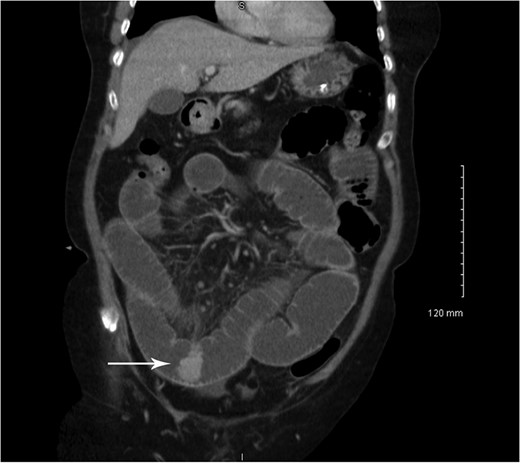

Coronal CT showing small bowel mucosal-enhancing lesion (arrow).